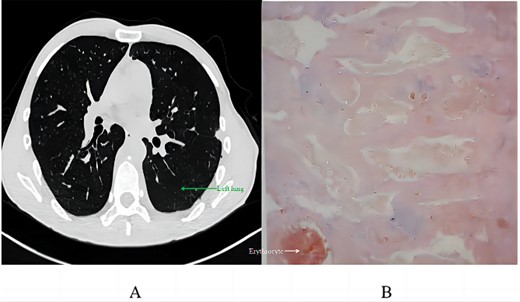

Postoperative recovery involved 420 ml of milky pleural drainage in the first day, suggestive of chylothorax. The patient followed a fat-free diet, leading to the resolution of chylous drainage by Day 12, at which point he returned to a normal diet. A chest CT on Day 14 demonstrated successful lung re-expansion without pleural effusion, permitting the removal of the chest tube. He was discharged the day after. Pathological analysis revealed vascular-like structures with red blood cells, minimal lymphocytes, consistent with a vascular tumour, diagnosed as an angioma (Fig. 4B) after immunohistochemistry tests for SOX-10 and AE1/AE3 were negative.

Postoperative analysis: (A) chest CT scan 2 months post-discharge; (B) pathological section.

Two months after discharge, a follow-up CT scan revealed no significant pneumothorax, pleural effusion, or pneumonia, with no abnormal soft tissue in the surgical area. The patient noted a significant decrease in pain since discharge.